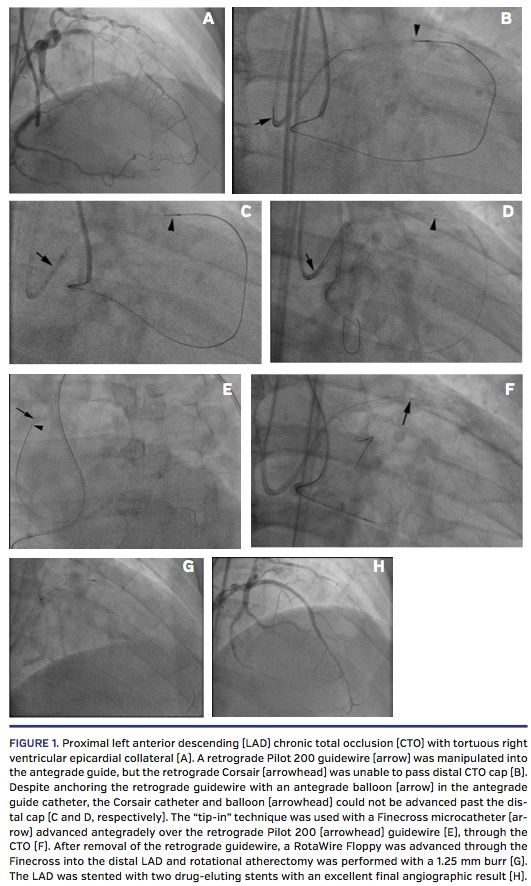

A 72-year-old man with Canadian Cardiovascular Society class-III angina despite maximal medical therapy was referred for PCI of a left anterior descending (LAD) artery CTO. The CTO was calcific and long with an ambiguous proximal cap and a J-CTO score of 3. The distal vessel was filled by CC25 epicardial collaterals from a right ventricular (RV) branch (Figure 1A). Vascular access was established using bilateral femoral 7 Fr, 35-cm long sheaths. AL3 and XB3.5 7 Fr guides were

used to engage the right coronary and left main coronary arteries, respectively. Because of the proximal cap ambiguity, the initial strategy was retrograde approach using the epicardial collaterals. A Corsair catheter (Asahi Intecc) was advanced into the RV branch over a workhorse wire. A Sion guidewire (Asahi Intecc) successfully traversed the collateral vessel into the mid LAD and was advanced to the distal cap followed by the Corsair microcatheter. A Pilot 200 guidewire (Abbott Vascular) was used to puncture the distal cap, and subsequently crossed the CTO segment into the proximal LAD. We were able to advance the Pilot 200 guidewire into the antegrade left main guide catheter, but were unable to advance the Corsair or a balloon retrogradely through the distal cap (Figure 1B), in spite of anchoring the retrograde wire in the antegrade guide catheter (Figures 1C and 1D). We then performed the tip-in technique by advancing a Finecross microcatheter (Terumo Corporation) in the antegrade guide catheter and inserting it over the retrograde wire (Figure 1E). We were then able to advance the Finecross antegradely on the retrograde guidewire through the occluded segment to the distal cap (Figure 1F). The retrograde guidewire was exchanged for a RotaWire Floppy (Boston Scientific) and advanced through the Finecross into the distal LAD and rotational atherectomy was performed using 1.25 burr at 160,000 rpm (Figure 1G). The LAD was then stented with 3.0 x 32 mm and 2.75 x 38 mm Promus Premier stents (Boston Scientific), followed by postdilation with a 3.5 mm non-compliant balloon with excellent angiographic result (Figure 1H). The patient had no postprocedural complications and was angina free on follow-up.